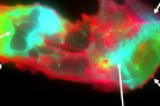

In the Journal of Medical Virology study, blood plasma from long COVID patients showed microclots that are not only more numerous but also larger compared with healthy controls.

Researchers observed NETs physically embedded within microclots in long COVID samples, a finding that could make clots more resistant to the body's fibrinolysis process.

Imaging flow cytometry and fluorescence microscopy were used on blood samples from 50 long COVID patients and 38 healthy volunteers across France and South Africa, revealing a consistent pattern.